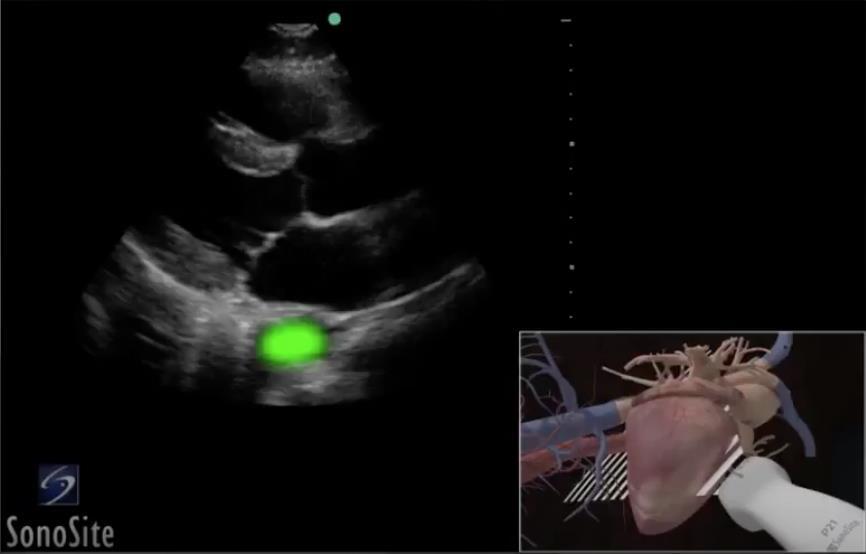

Heart Parasternal Long Axis (PLAX) Highlighted Aorta Image

Highlighted Area: Aorta